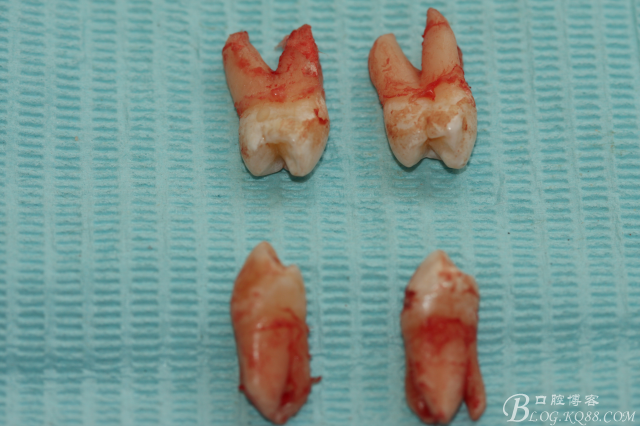

5.上頜離體第一前磨牙牙根形態(tài)

6.下頜離體第一前磨牙牙根形態(tài)

7.四顆離體上下頜第一前磨牙牙根形態(tài)